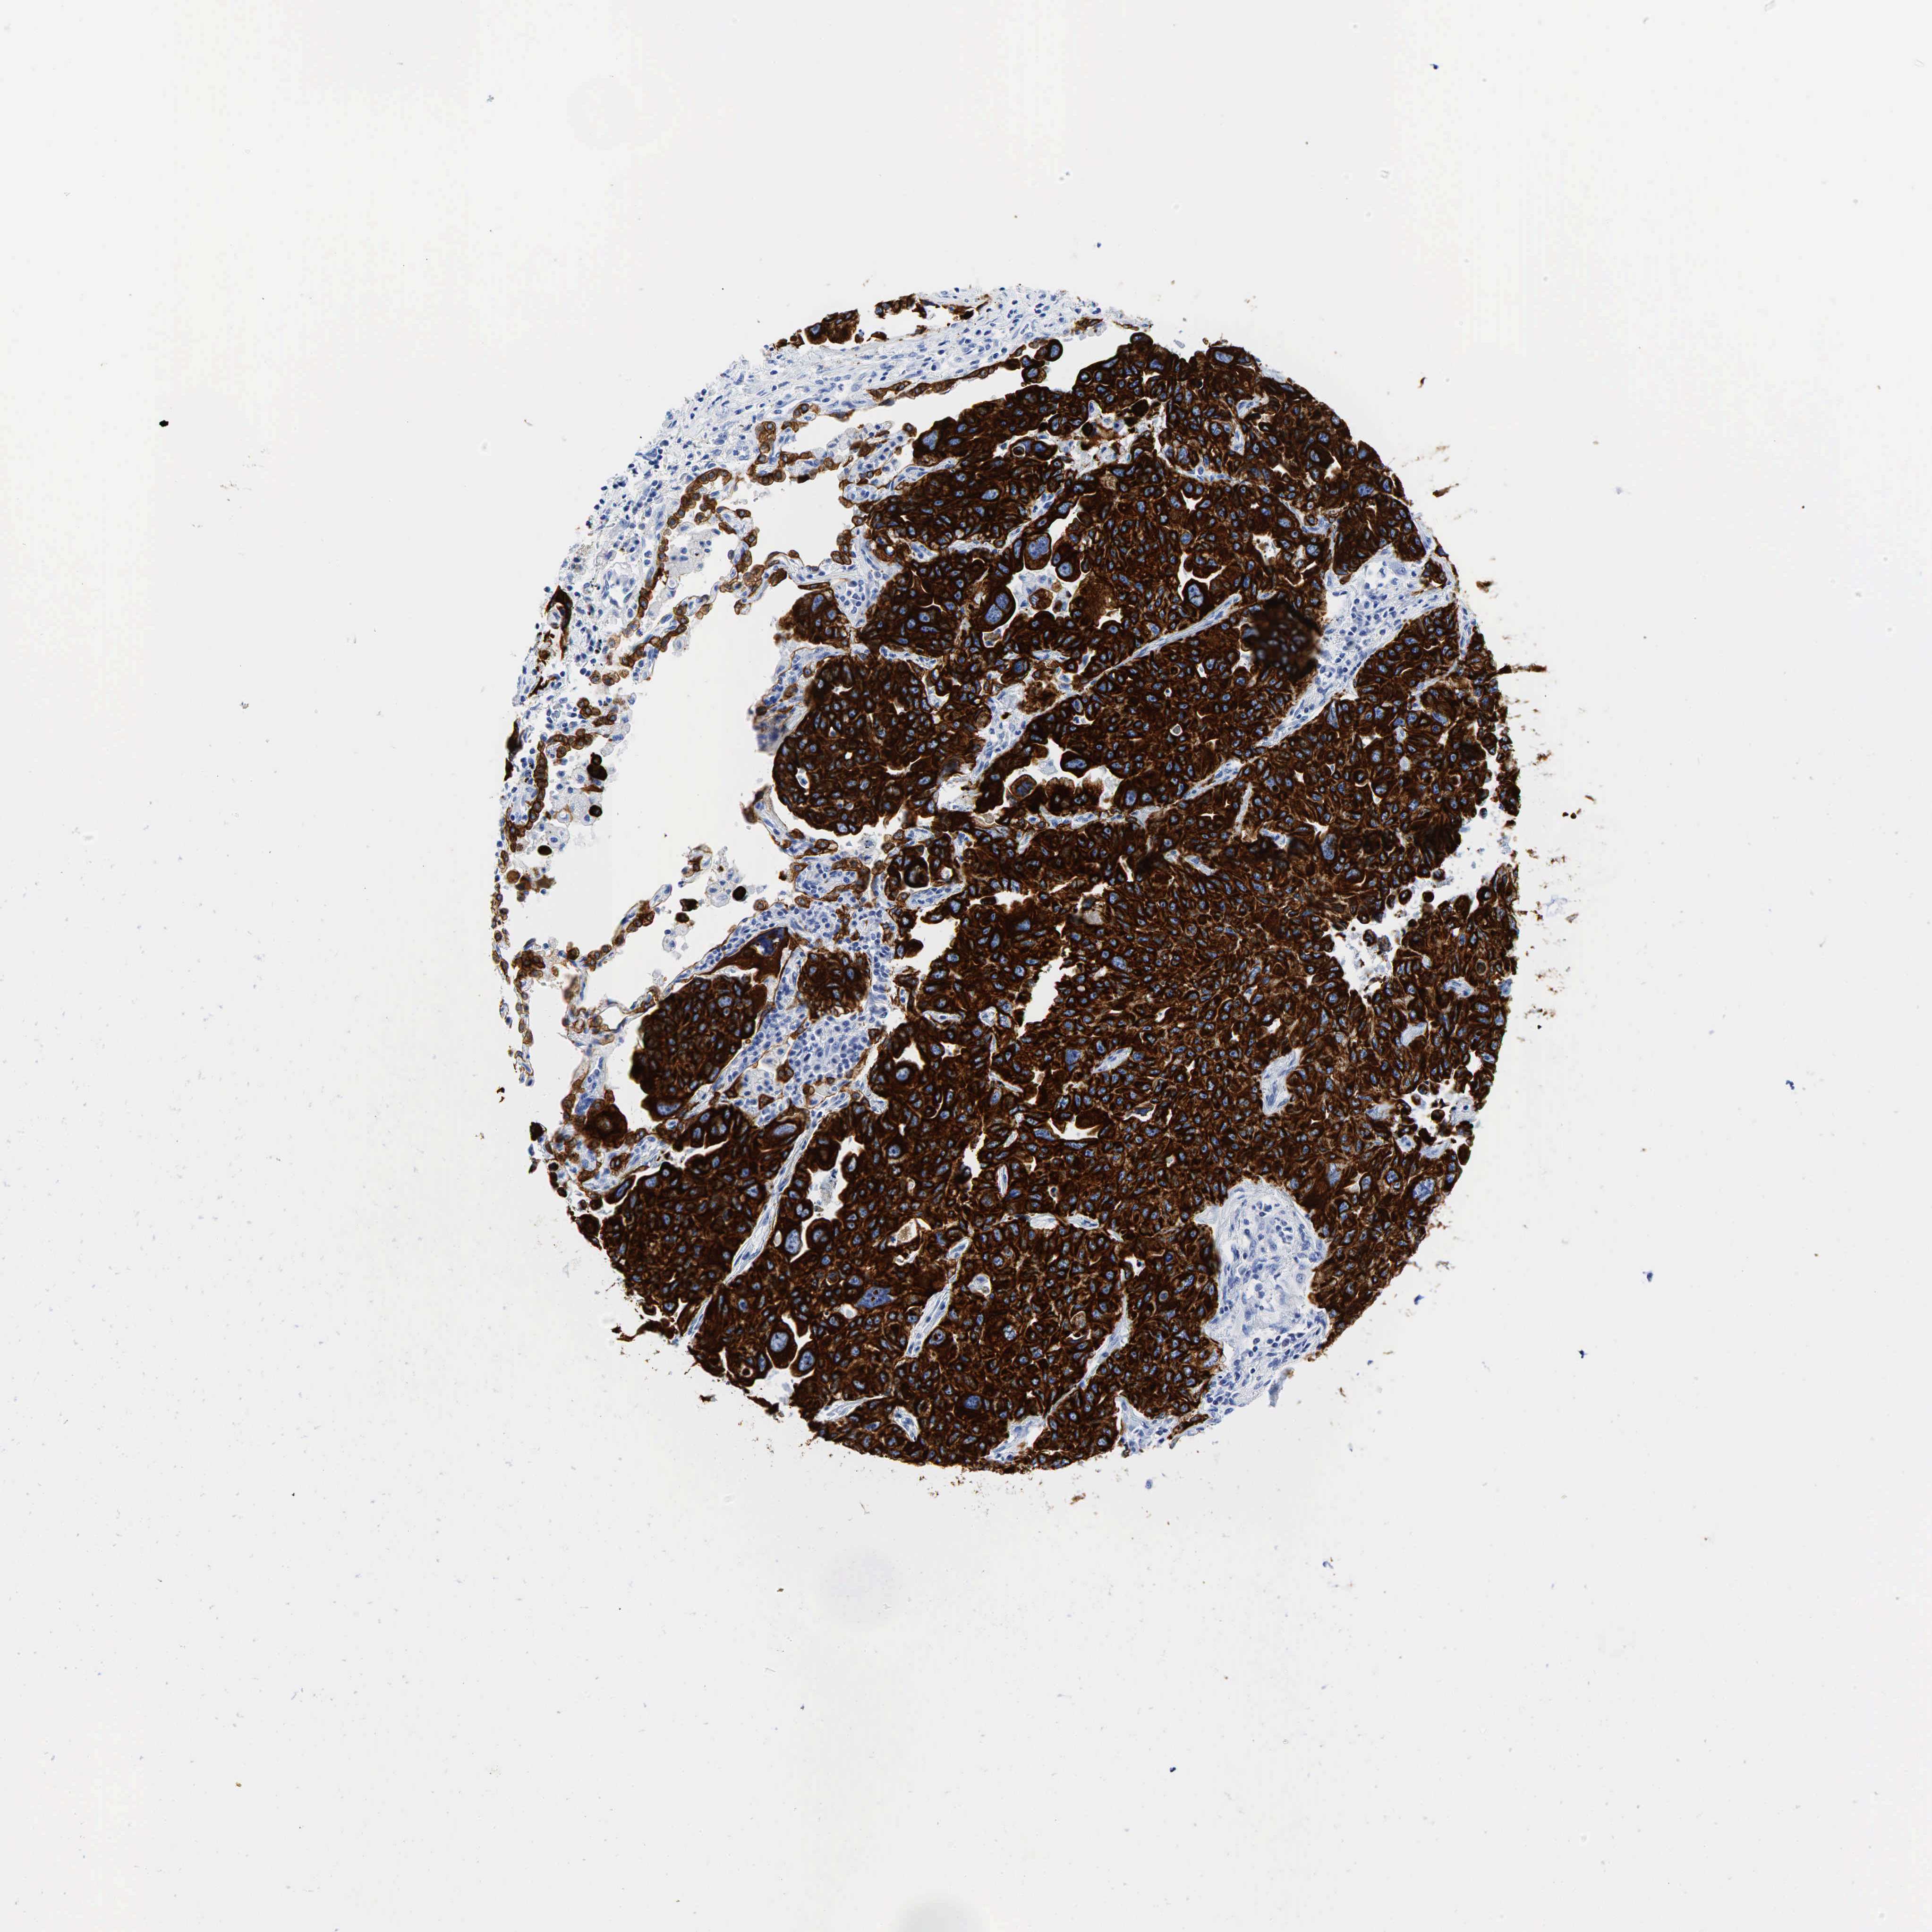

LUNG SQUAMOUS CELL CARCINOMA (TCGA) - Interactive survival scatter ploti

KRT18 is not prognostic in Lung Squamous Cell Carcinoma (TCGA)